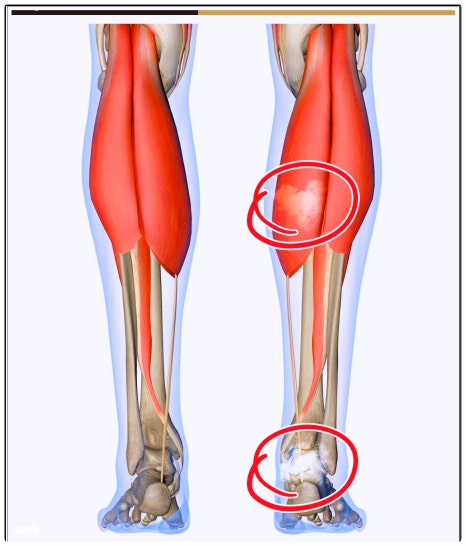

고관절과 발의 영향

고관절이 안쪽으로 말리거나(내회전),

발목이 평평하게 눌린(평발) 상태라면

지면에서 오는 충격이 그대로 무릎으로 전달됩니다.

결과적으로 무릎의 충격 흡수 능력이 떨어지고

연골 마모 속도는 더 빨라지죠.

고관절 회전 불균형은 골반과 척추까지 영향을 미쳐

무릎 정렬까지 비틀리게 만듭니다.

즉, 척추–골반–고관절–무릎–발목은 하나의 체인처럼 연결되어 있어

한 부위 균형이 무너지면 연골이 받는 압력도 비정상적으로 높아집니다.